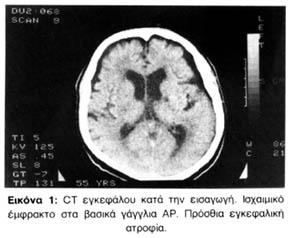

Σταδιακά η ασθενής παρουσίασε βελτίωση της κινητικότητας, με διακυμάνσεις όμως του επιπέδου της συνείδησης. Το συναίσθημα ήταν απρόσφορο (γέλιο-κλάμα), η συμπεριφορά εναλλασσόμενη από επιθετική και οργίλη ως αμίλητη και αρνητική. Στη συνέχεια εμφάνισε πάλι δεξιά ημιπάρεση και ανισοκορία (μυδρίαση ΑΡ). Περιέπεσε σε κατάσταση stupor και είχε αναπνοή Cheyne-Stokes. Στην νέα CT εγκεφάλου, που έγινε επειγόντως (14/6/95), φάνηκε υπόπυκνη τριγωνική εστία στην ΑΡ κροταφοβρεγματική περιοχή. Τα ευρήματα από την προηγούμενη CT παρέμειναν ως είχαν (εικόνα 2).